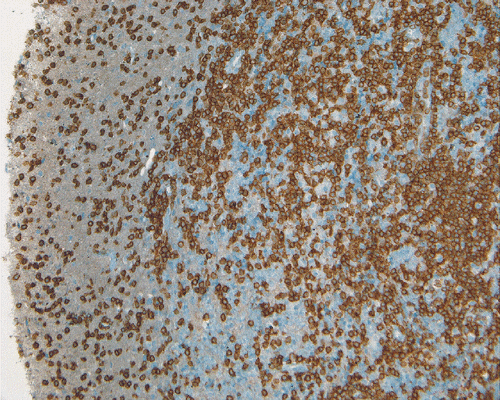

LCA

N.